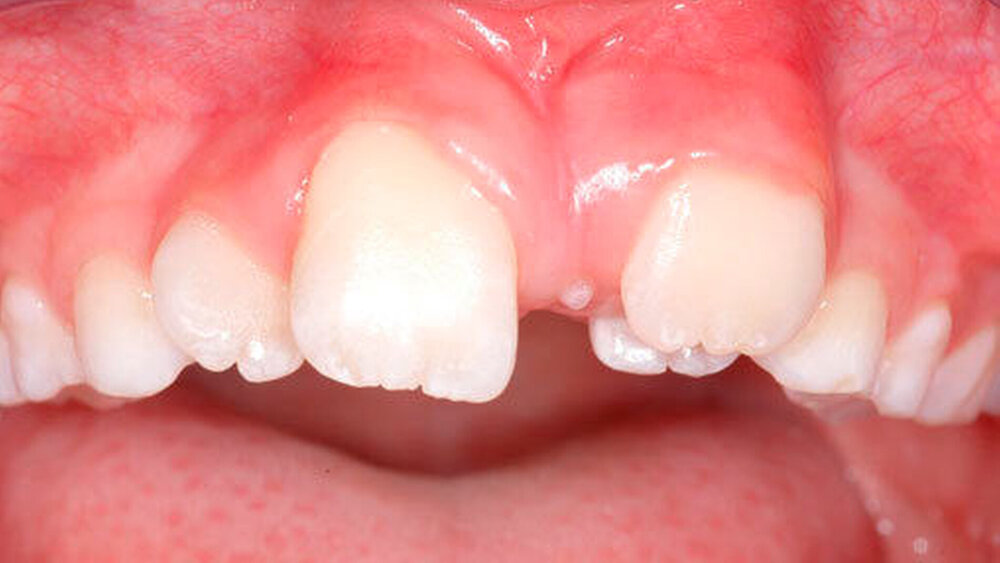

Überzählige Zähne sind die häufigste Ursache für einen unterbliebenen oder verzögerten Durchbruch der oberen Schneidezähne (Abbildungen 13, 14, 15) [Betts Camilleri, 1999]. Besonders beim höckerförmigen Typ kommt es häufig zu Störungen der Eruption der oberen Schneidezähne [Mason et al., 2000]. Diese Komplikation macht sich klinisch initial dadurch bemerkbar, dass die oberen seitlichen Schneidezähne durchbrechen und die Eruption von einem oder beiden zentralen Schneidezähnen ausbleibt [Rajab Hamdan, 2002]. Auch in anderen Lokalisationen der Kiefer können überzählige Zähne zu Durchbruchsstörungen benachbarter Zähne führen [Garvey et al., 1999; Rajab Hamdan, 2002; Mossaz et al., 2014]. Insgesamt liegt die Prävalenz für den Ausfall des Durchbruchs bleibender Zähne bedingt durch überzählige Zähne zwischen 10,2 Prozent und 61 Prozent [Tay et al., 1984; Koch et al., 1986; Tyrologou et al., 2005; Fernández Montenegro et al., 2006; Liu et al., 2007; Gündüz et al., 2008; Hyun et al., 2009; Mínguez-Martinez et al., 2012; Mossaz et al., 2014].

Überzählige Zähne können bei Nachbarzähnen von einer leichten Rotation bis hin zu einer körperlichen Verschiebung alle Formen der Lageveränderungen bewirken. Studien zeigen auf, dass etwa bei einem Drittel der überzähligen Zähne eine Verschiebung des benachbarten Zahns resultiert [Koch et al., 1986; von Arx, 1990; Tyrologou et al., 2005; Liu et al., 2007; Gündüz et al., 2008; Mossaz et al., 2014]. Tay und Mitarbeiter (1984) berichteten gar über eine noch höhere Prävalenz von 55 Prozent. Hyun und Mitarbeiter (2009) betonen, dass überzählige Zähne im Oberkieferfrontzahnbereich nicht selten auch zu einer Diastemabildung führen, was für die Therapieplanung von Bedeutung ist (Abbildungen 16 uns 17).

Bei überzähligen Zähnen werden vier morphologische Typen unterschieden: konisch (Abbildung 9), tuberkulär (höckerförmig; Abbildung 10), überzählige Zähne mit identischer Zahnform (Abbildung 11) und Odontom (Abbildung 12) [GARVEY et al. 1999]. Der konische überzählige Zahn ist ein kleiner, zapfenförmiger Zahn und zudem der häufigste Fall im bleibenden Gebiss [Rajab Hamdan 2002, Liu et al. 2007, Gündüz et al., 2008; Ferrés-Padró et al., 2009; Hyun et al., 2009; Schmuckli et al., 2010; Mossaz et al., 2014]. Er kommt oft zwischen den oberen zentralen Schneidezähnen vor und entwickelt sich gleichzeitig zur Wurzelbildung der bleibenden Schneidezähne. Konische überzählige Zähne führen meist nicht zu einer Durchbruchstörung oder -behinderung der zentralen Schneidezähne. Tuberkuläre, überzählige Zähne sind größer als der konische Typ und besitzen einen zusätzlichen charakteristischen Höcker oder Tuberkel der Zahnkrone. Sie kommen oft gepaart vor und liegen in der Regel palatinal der oberen mittleren Schneidezähne. Im Gegensatz zu konischen überzähligen Zähnen brechen die meisten tuberkulären nicht in die Mundhöhle durch und es kommt nicht selten zur Durchbruchstörung oder -behinderung der zentralen Schneidezähne [Mason et al., 2000; Minguez-Martinez et al., 2012]. Überzählige Zähne mit identischer Zahnform sind Zähne, welche vom eigentlichen Zahn in der Lage (also in der Zahnreihe gelegen) und Form nicht zu unterscheiden sind.